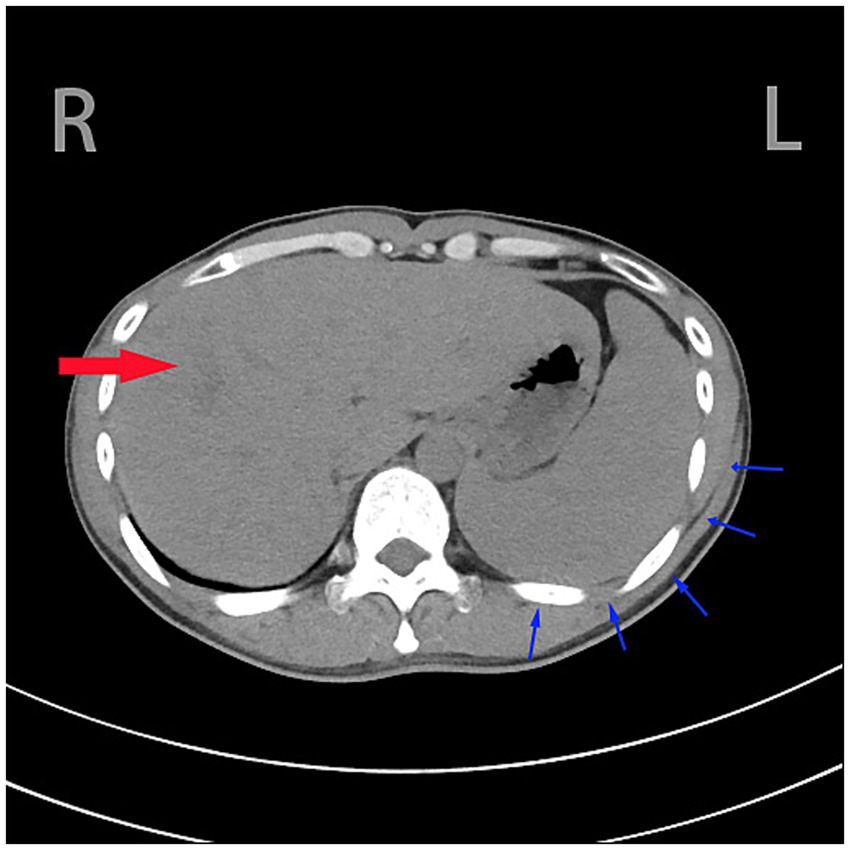

Routine abdominal ultrasound revealed hypoechoic areas at the gallbladder fundus, suggesting bile stasis and sludge formation. Abdominal CTA showed portal hypertension, lower esophageal varices, splenomegaly, uneven liver parenchymal density, and mild dilation of the intrahepatic bile ducts (Figure 1).

Figure 1. Heterogeneous hepatic parenchymal density is observed (denoted by red arrow), accompanied by splenomegaly with the splenic outer margin extending beyond five rib units (indicated by blue arrow).